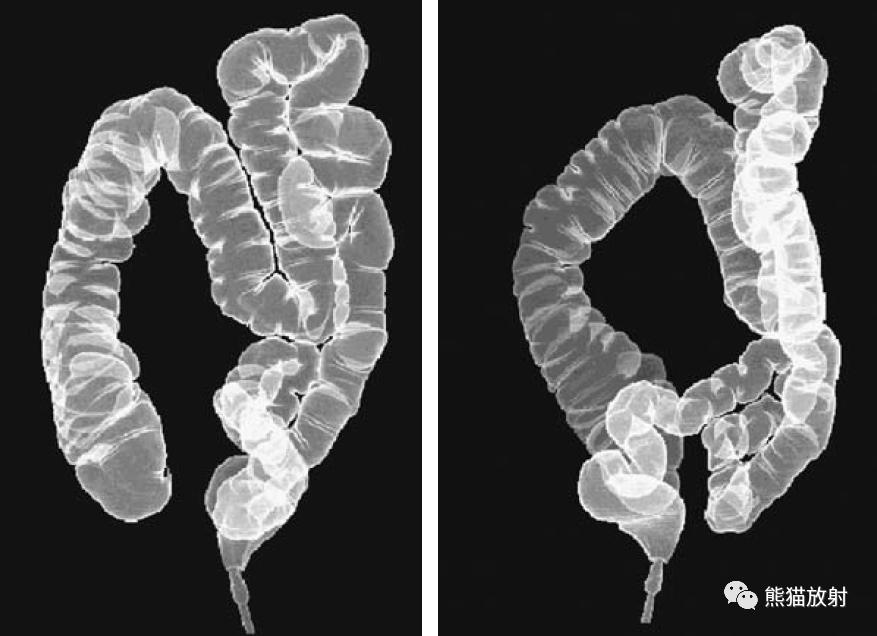

3D CT双对比虚拟结肠镜检查的两个视图。可以从空间上的任何角度来分析图像。

两张3D双对比MR虚拟结肠镜图像。可视化类似于使用CT获得的可视化